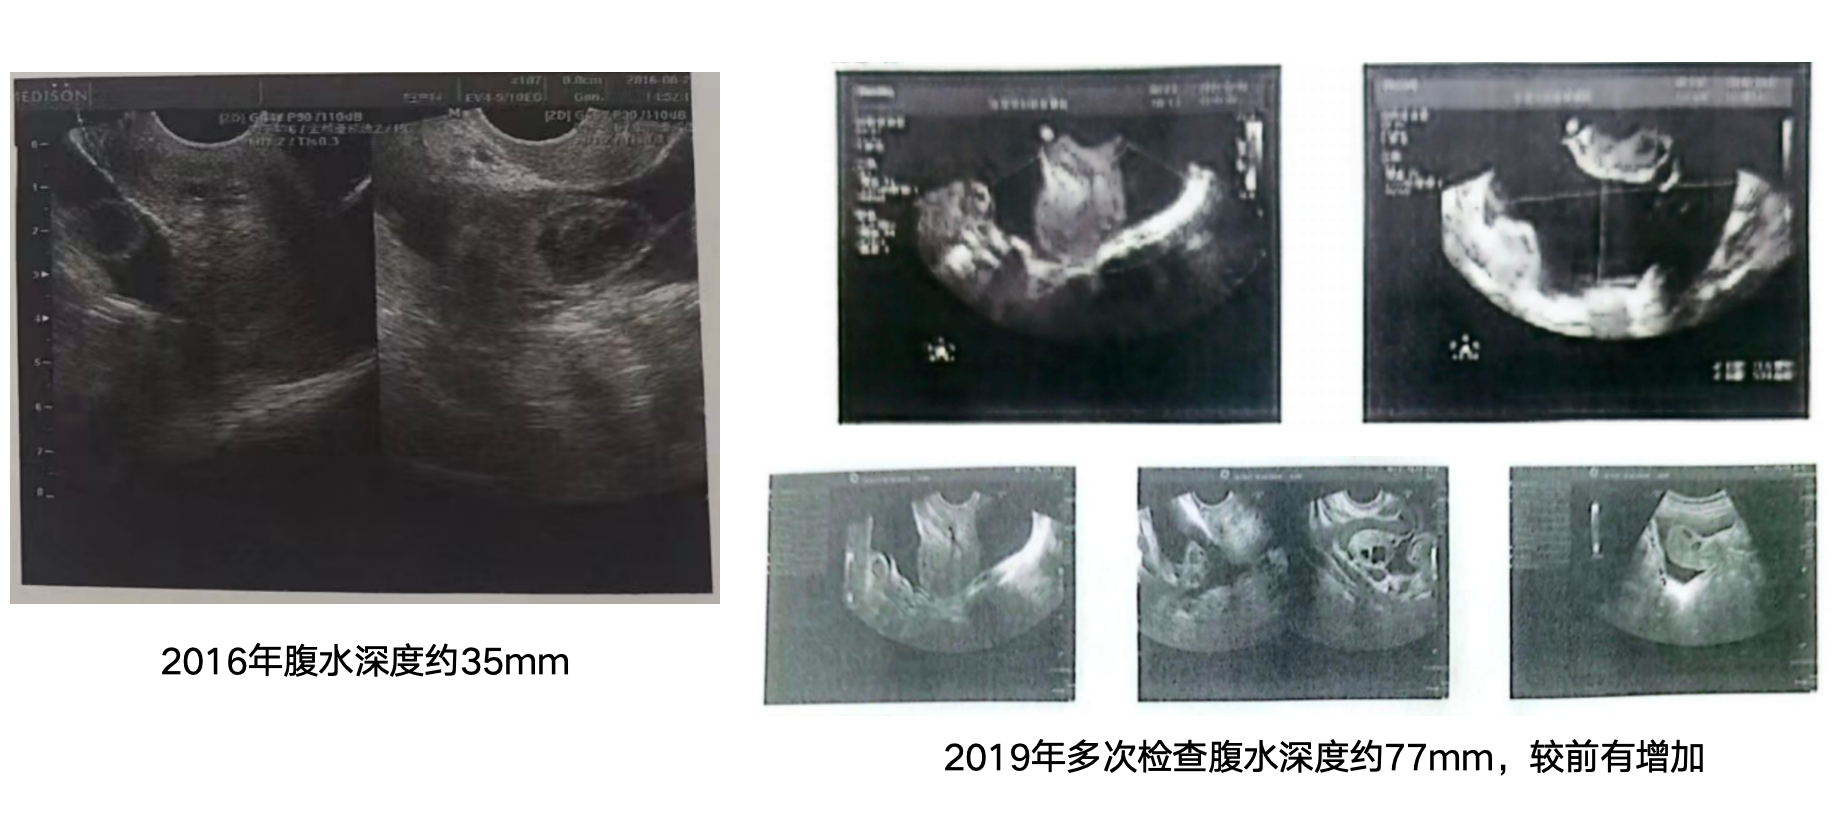

33岁女性,规律性生活后未孕10余年,因生育需求就诊。2016-2019年外院多次B超检查示“盆腔积液”。5岁时(28年前)曾因蛔虫导致肠梗阻行开腹肠切除术。